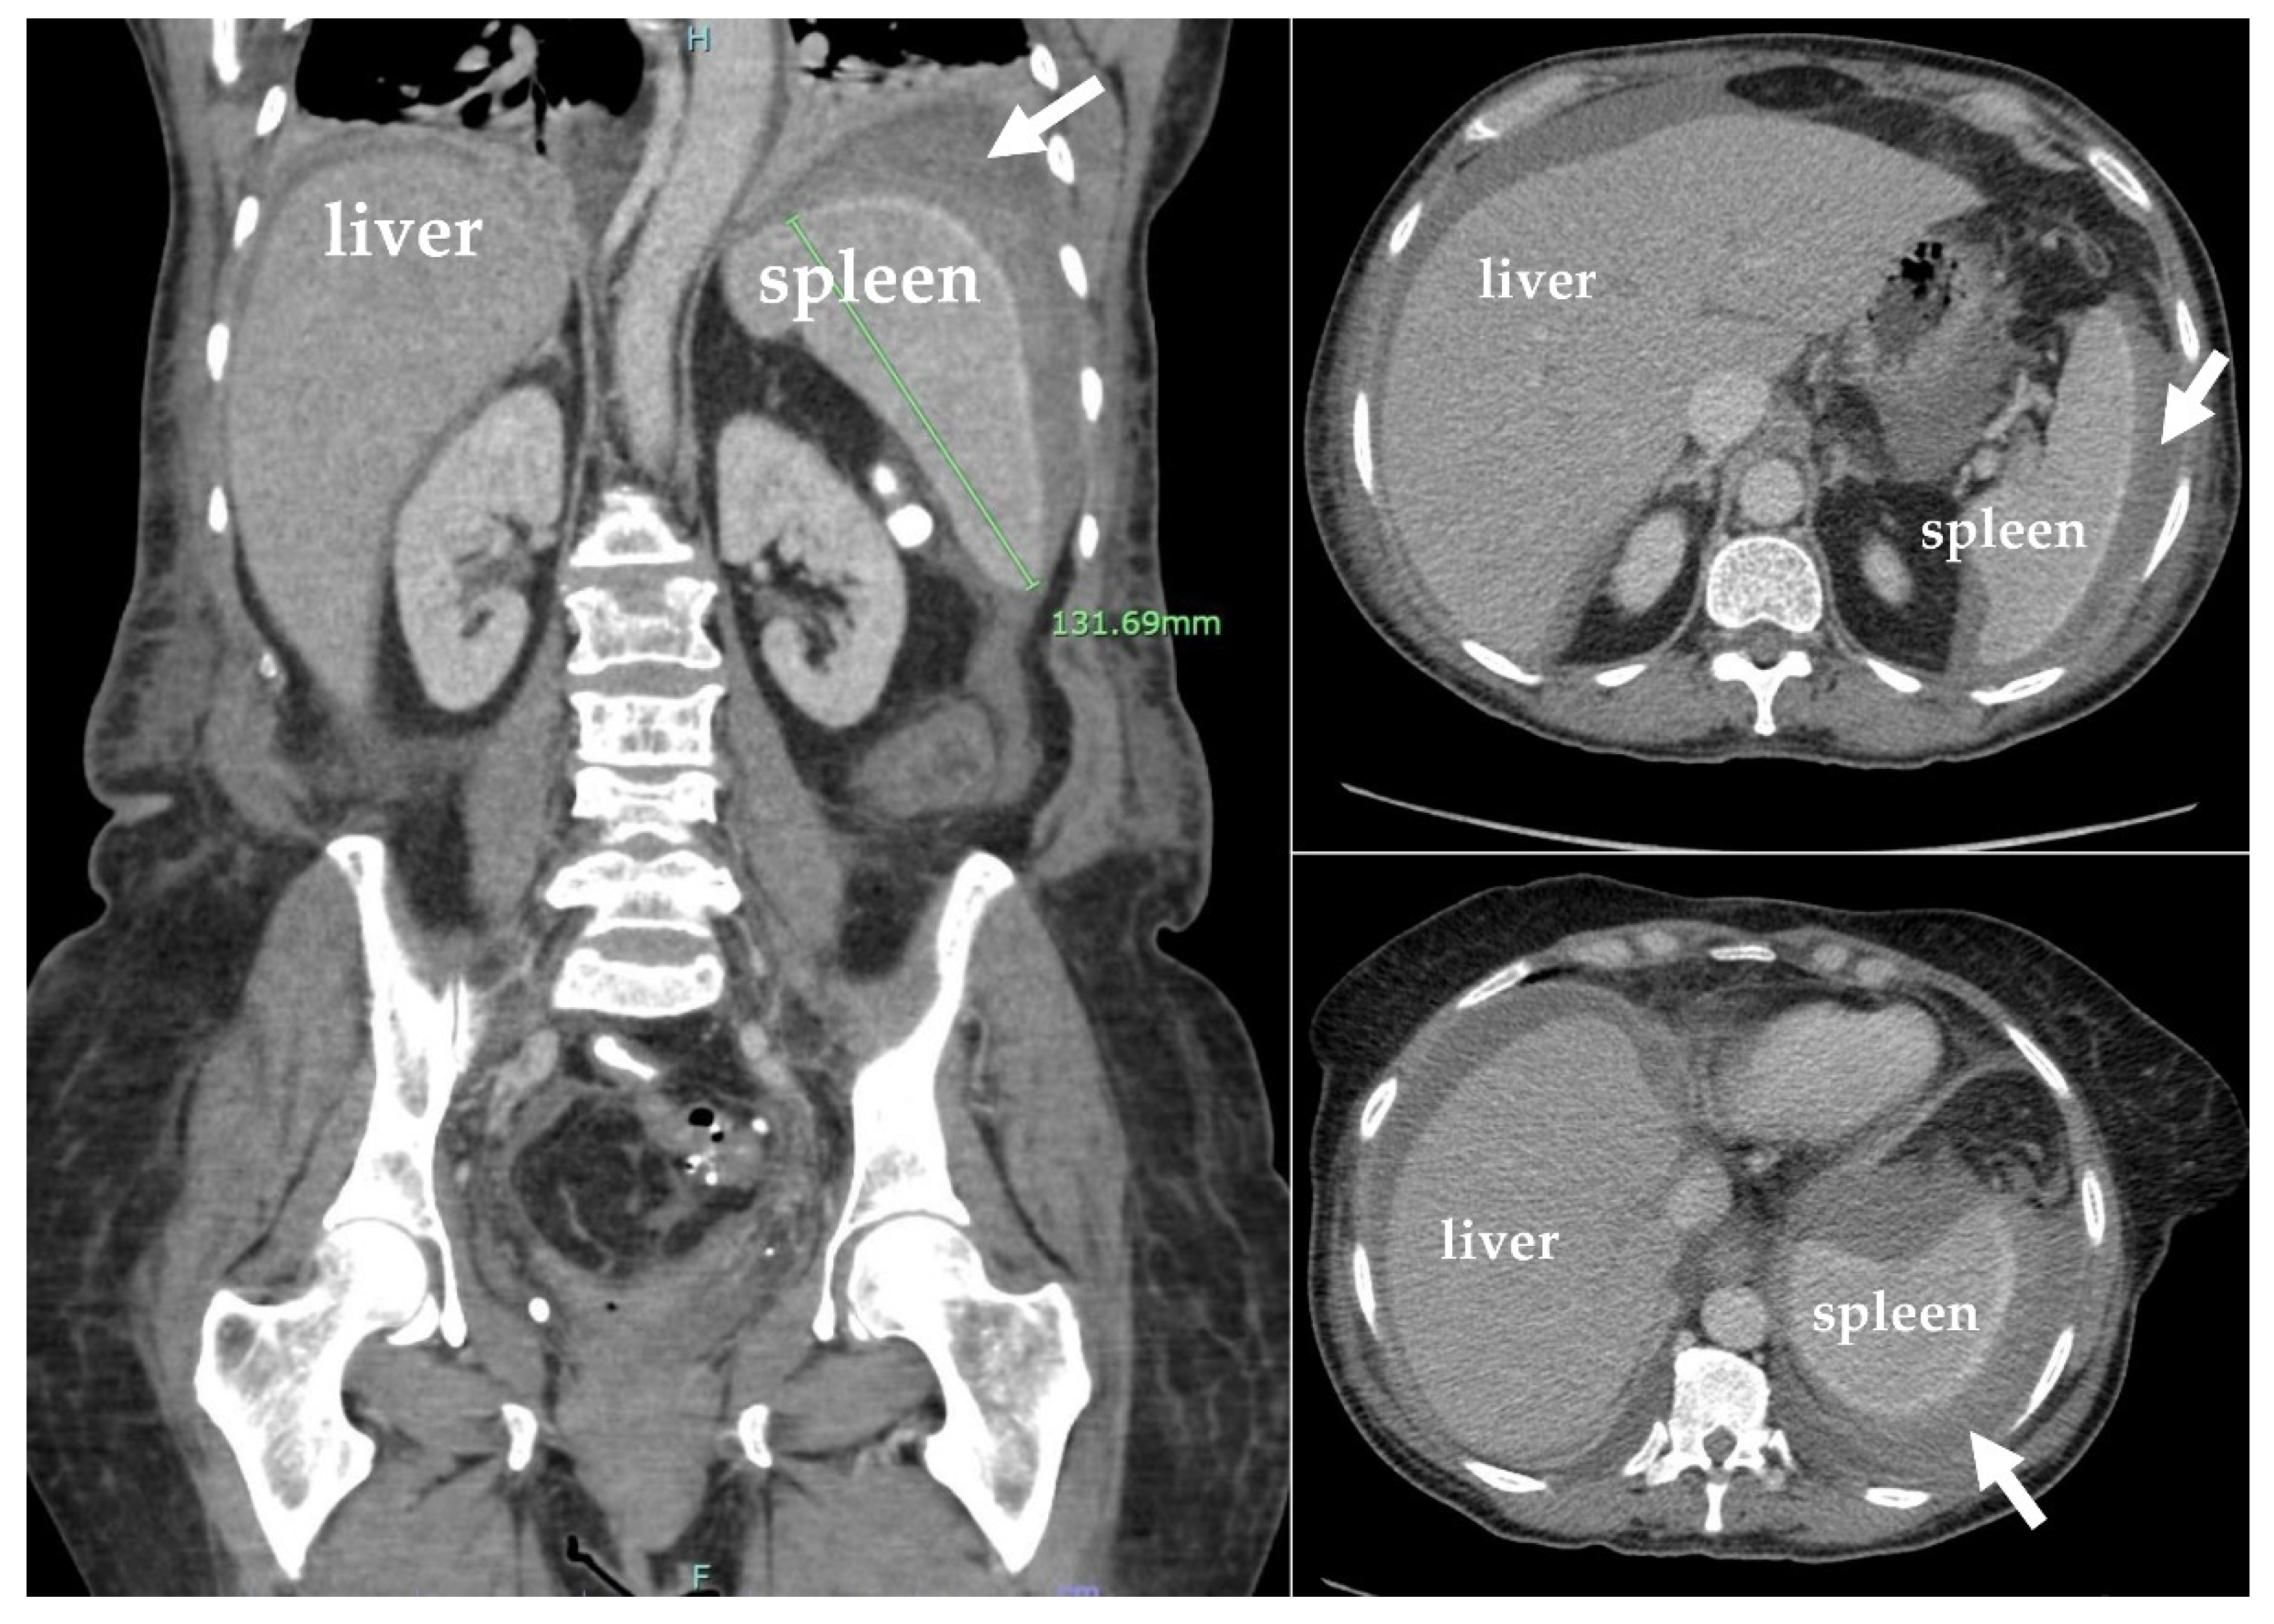

A CTA of the abdomen and pelvis was performed and showed an increase in the size of the splenic subcapsular hematoma, measuring approximately 14.0 × 13.2 × 6.1 cm, and large splenic infarction (Figure 5). Given the new imaging findings and intractable left abdominal pain, the surgery team was consulted. Accordingly, the patient was taken to the operation room for open splenectomy due to splenic rupture and hemorrhage. The spleen was then taken to pathology. On histopathological examination, the spleen was enlarged, weighing 593 g and measuring 16 × 10 × 5.2 cm. The capsule was dark red and had a predominantly posterior laceration, which measured 13.5 cm. Multiple adhesions were also noted (Figure 6A). The cut section revealed a poorly demarcated, dark red, hemorrhagic area located superiorly in the subcapsular area and measuring 10.5 × 7 × 4 cm. Additionally, identified were multiple ill-defined, firm, white-yellow areas comprising approximately 10% of the total cut surface. The remainder of the spleen parenchyma was homogeneous, dark red, and firm (Figure 6B).

Figure 5. Coronal and sagittal plane computed tomography angiogram (CTA) scans with IV contrast of the abdomen and pelvis showing large splenic infarction with an increase in the size of splenic subcapsular hematoma, measuring up to approximately 14.0 × 13.2 × 6.1 cm, with a mass effect on the splenic parenchyma and an increase in the moderate-volume hemoperitoneum.